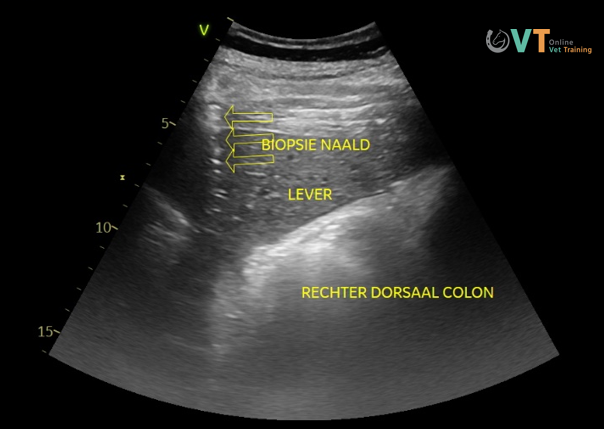

- Gezien de combinatie van leverafwijkingen en lymfadenopathie werd onder echografische begeleiding een leverbiopsie uitgevoerd.